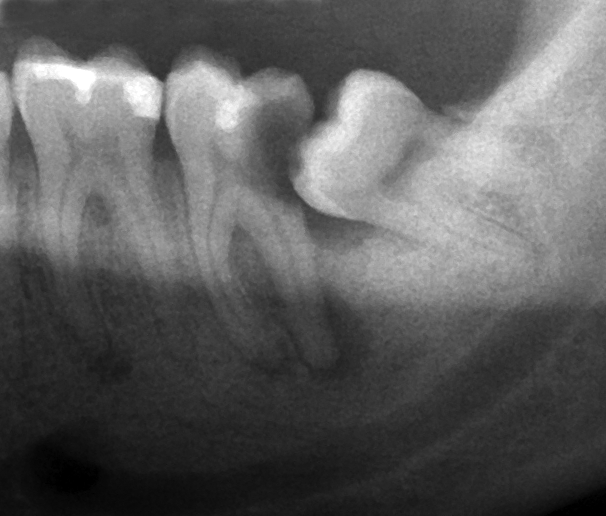

Tooth decay happens due to the food trap that results from the impacted wisdom tooth. This results in hidden decay that only presents when severe pain occurs. This usually results in loss of both the wisdom tooth and the 2nd molar, which will impact function significantly.